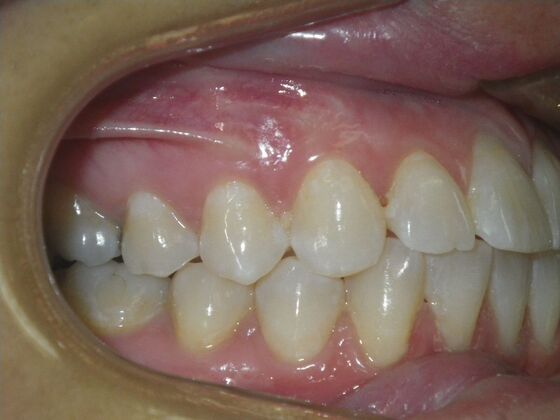

Invisalign: Case 18

This patient had concerns with the lower anterior teeth. There were some slight rotations and the midline of the lower incisors wasn't lined up with the upper midline. To correct this we used slenderizing of teeth in strategic areas of the lower arch to correct the rotations and line up the midlines. Patient very pleased with the results.